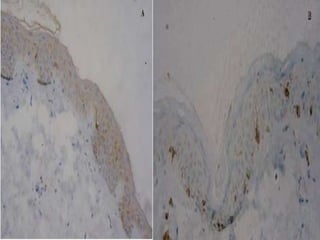

(A)Significantly decreased number of CD1a

positive cells (inbrown) in the non-lesional

skin of active vitiligo patients.

(B)In contrast, there are abundant marked CD1a

positive cells in the control skin.

(A)Presence of CD8+ cells infiltrate in the dermis

of nonlesional skin in active vitiligo.

(B)Such infiltrate was not observed in any

control skin.